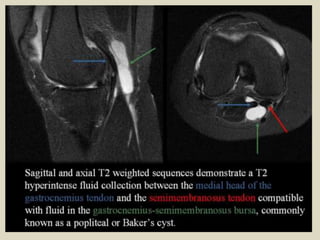

Baker's Cyst

This is also called a popliteal cyst and typically involves the gastrocnemius- semimembranosus bursa and

is located between the medial femoral condyle, semimembranosus tendon and the medial head of the

gastrocnemius. It may or may not communicate with the knee joint. It may rupture and extend inferiorly

along the gastrocnemius muscle into the calf or extend superiorly into thigh along the semimembranosus.

On MRI they appear as well-defined hyperintense lesions on T2W images at the characteristic location.

Axial images are the best to demonstrate the communication with the knee joint and also the

characteristic location between the semimembranosus tendon and medial head of gastrocnemius.